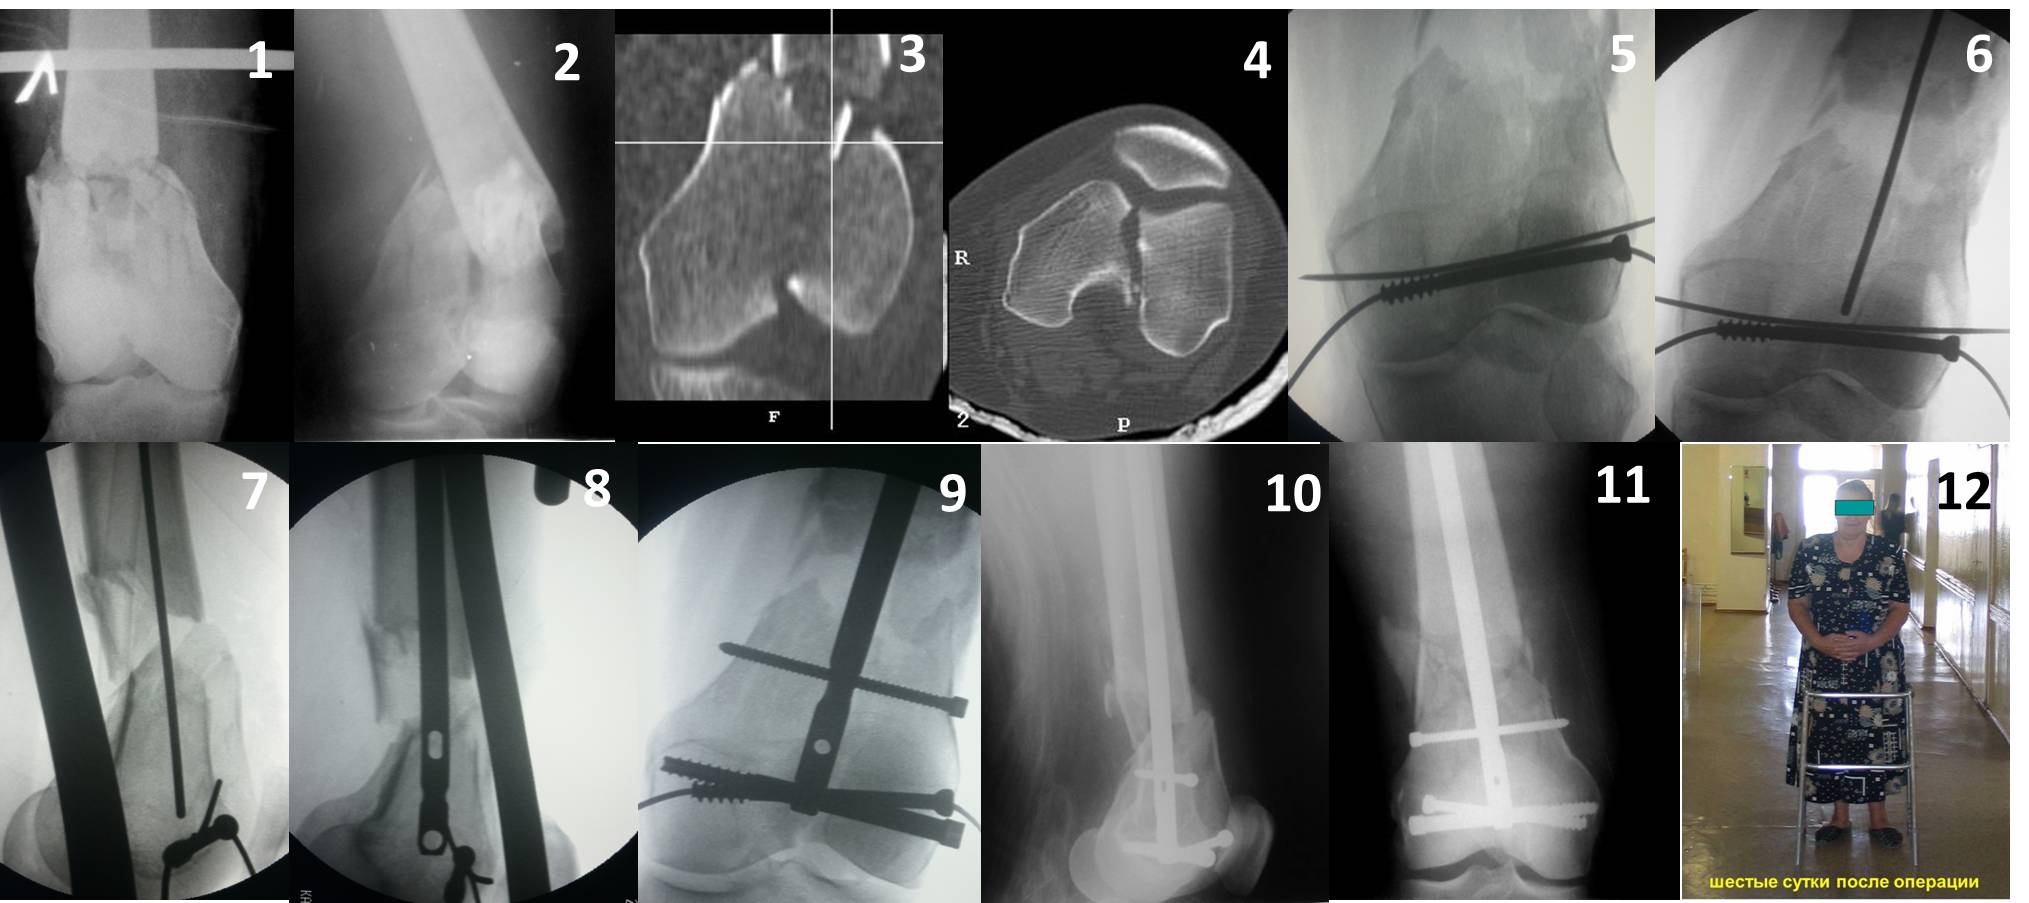

Ответ на эту часть Вашего поста – вложенный файл. Больная оперирована неделю назад по поводу открытого перелома дистального эпиметафиза бедренной кости. После операции она идёт в рентгенкабинет для выполнения послеоперационной контрольной рентгенографии, представленной на слайдах 10 и 11. Узнав, почему её фотографируют, просила передать Вам, Антон, привет.